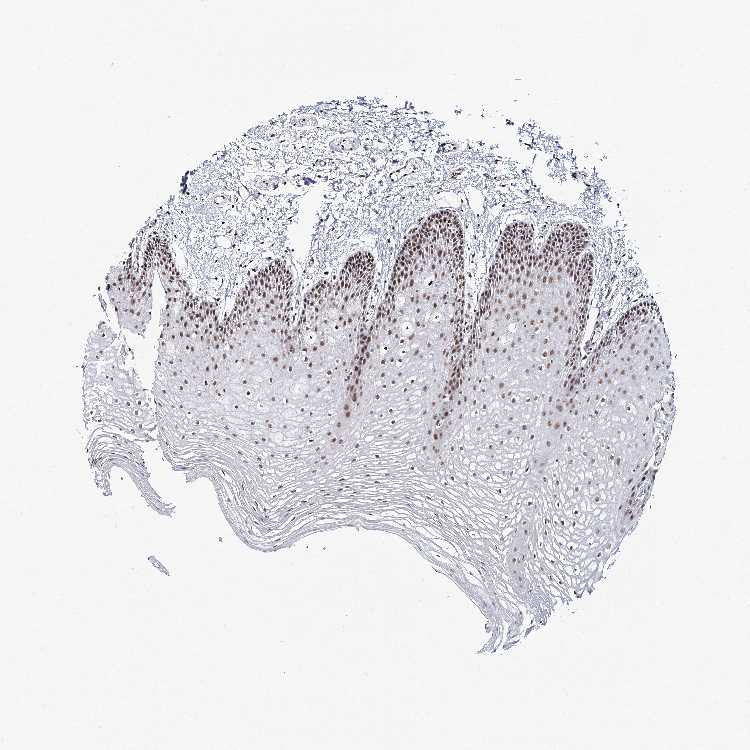

TISSUE PRIMARY DATA ORAL MUCOSA Show tissue menu

Oral mucosa

ORAL MUCOSA - Antibody stainingi

Antibody staining in the annotated cell types in the current human tissue is reported as not detected, low, medium, or high, based on conventional immunohistochemistry profiling in selected tissues. This score is based on the combination of the staining intensity and fraction of stained cells.

Each image is clickable and will lead to virtual microscopy that enables deeper exploration of all samples and also displays staining intensity scores, fraction scores and subcellular localization as well as patient and tissue information for each sample.

Antibody HPA035601Antibody HPA035602

Squamous epithelial cells HighHigh